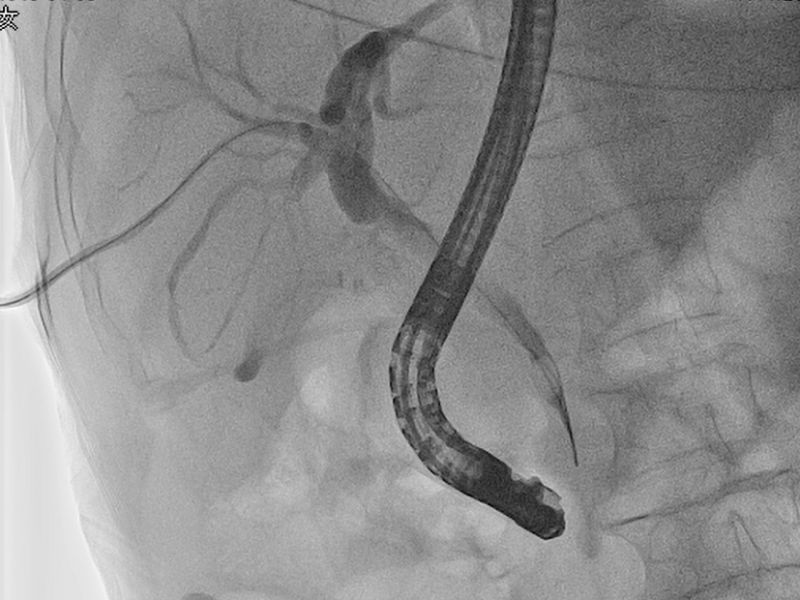

1月14日,在介入科、麻醉科多学科协助下,介入科丁文金副主任医师经PTCD管植入导丝及鞘管至十二指肠乳头开口处,消化内二科向仍运医师在十二指肠镜直视下插入导丝至PTCD鞘管成功会师,从而进入胆总管,切开十二指肠乳头,网篮取净胆总管结石,手术成功,拔除PTCD管。术后常规抗炎及支持治疗,患者康复顺利,于1月23日痊愈出院。

网篮取胆总管结石